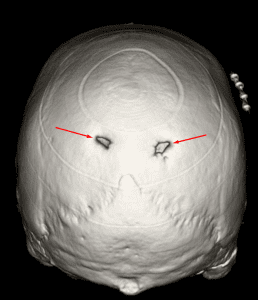

3D reconstruction demonstrating bilateral enlarged parietal foramina

Enlarged Parietal Foramina

Mimicking pathology